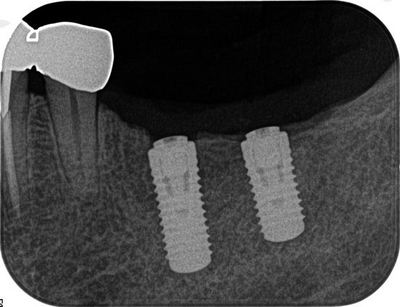

1本目の埋入が終わった時点でレントゲンで確認をします。

![]()

手前のインプラントの軸を基準に奥側のドリリングを終えました。

クリアランス確保のため骨頂をおよそ3mm下げてフラットニングしています。